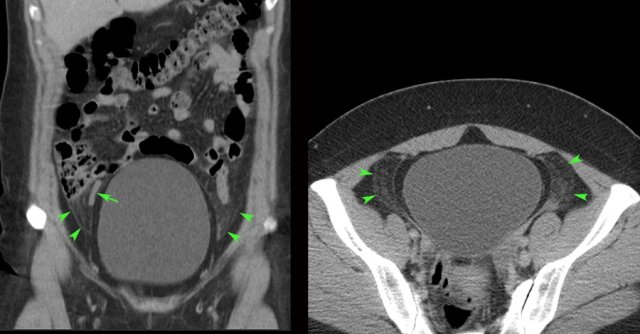

case 1

This pregnant

patient presented with acute LLQ pain.

US revealed an intact pregnancy of 8 weeks

and left of the uterus a painful, non-compressible (arrowheads), partly cystic,

partly solid mass, suspect for adnexal torsion.

At

laparoscopy a 360 degrees torsion of a luteal cyst was found.

After detorsion

the liquid component was aspirated.

case 2

A 21-week pregnant woman was submitted with suspected appendicitis. She had similar attacks before.

US shows an intact pregnancy and in the right lower quadrant a large dermoid cyst (arrowheads).

laparotomy the dermoid cyst was oedematous, probably due to intermittent torsion.

Ovary-sparing resection was successful.